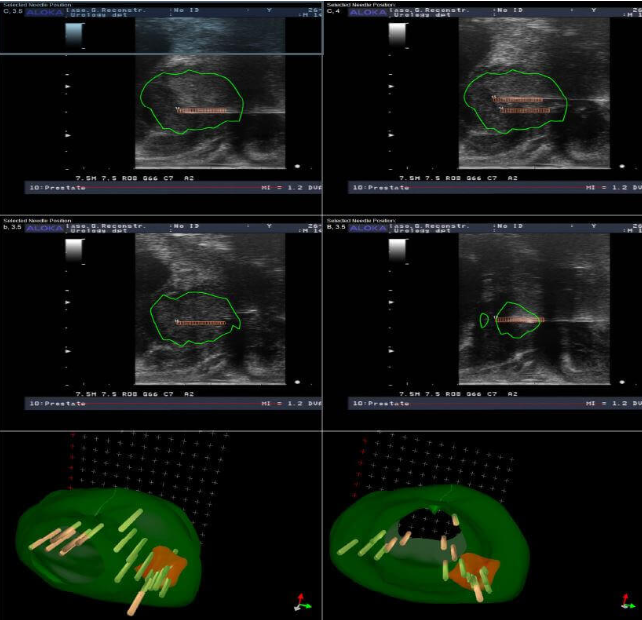

Εγώ με την ομάδα μου ακολουθούμε απο το 2016-που για πρώτη φορά στην Ελλάδα ξεκινήσαμε αυτού του τύπου την θεραπεία και κάθε χρόνο παρουσίαζουμε στα διεθνή συνέδρια τα παοτελέσματα μας ,έχοντας πλέον μία αξιοπρόσεκτη εμπειρία-ένα σύνολο αυστηρών προτύπων στούς άνδρες που πρόκειται να λάβουν εστιακή θεραπεία. Αυτό περιλαμβάνει μια ενδελεχή αξιολόγηση δια μέσω πολυπαραμετρικής μαγνητικής τομογραφίας προστάτη και υβριδικών διαπερινεϊκών βιοψιών , το βαθμό κακοήθειας Gleason απο τις βιοψίες ,το PSA,την ηλικία ,τις συνοδές παθήσεις κ.α. για να επιβεβαιωθεί ότι ο όγκος είναι μικρός και εντοπισμένος και ότι μια πιο εκτεταμένη θεραπεία δεν είναι απαραίτητη όπως είναι π.χ. η χειρουργική ή η ακτινοθεραπεία ..png)

Τα είδη εστιακής θεραπείας που προσφέρουμε στους ασθενείς μας -και μόνο εφ’όσον πληρούν τα κριτήρια ένταξης στη κλινική μας μελέτη- είναι: